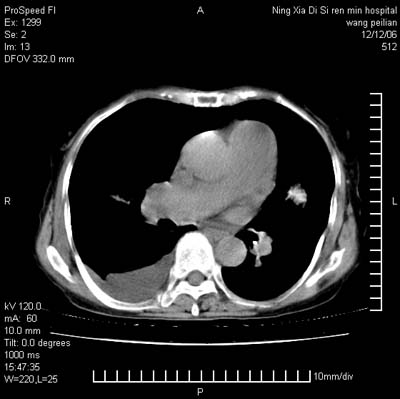

标题: CT5609:胸部:女77 病史不详

两肺可见多个大小不等的结节,左侧有胸水,纵隔淋巴结增大,考虑是细支气管肺泡癌

两肺尖纤维索状影,两下肺结节块状影,且有钙化灶,右胸腔积液。考虑肺结核并胸膜炎。

两肺尖纤维索状影,两下肺结节块状影,且有钙化灶,右胸腔积液。考虑肺结核并胸膜炎肺间质纤维化

考虑:1、慢性支气管炎合并全小叶型肺气肿、间质纤维化;

2、双肺结核;

3、右侧胸膜炎(积液)。

1、双肺继发型肺结核(以纤维、增殖灶为主);

2、右侧胸腔积液;

3、其余符合老年肺改变。

双肺见多个结节状及条索状影,双侧胸腔积液,右侧叶间积液,考虑结核性胸膜炎